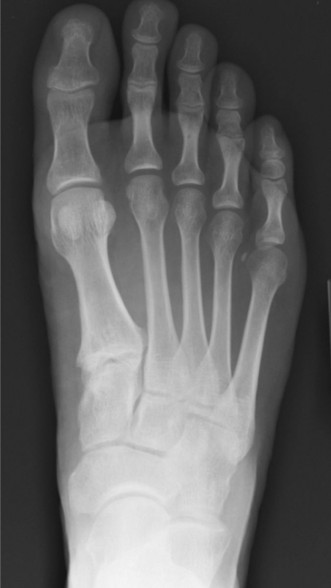

- Radiographs (X-rays): Essential initial imaging.

- Weight-bearing anteroposterior, lateral, and oblique views of the foot and ankle are standard.

- Medial Pain: May reveal pes planovalgus deformity (e.g., in PTTD), accessory navicular, osteophytes, stress fractures (navicular), or degenerative changes. Alignment views (e.g., Saltzman view) can quantify hindfoot alignment.

- Lateral Pain: May show fifth metatarsal base fractures (Jones, avulsion), cuboid subluxation, calcaneal stress fractures, or signs of chronic ankle instability (e.g., osteophytes, subtle widening of talar tilt).

- Radiographs (X-rays): These are the initial imaging modality for nearly all foot and ankle complaints.

- Standard views: Weight-bearing anteroposterior (AP), lateral, and oblique views of the foot are crucial to assess alignment, osseous integrity, and degenerative changes. Ankle views (AP, lateral, mortise) should be included if ankle pathology is suspected.

- Medial Foot Pain Imaging Insights: Radiographs may reveal an accessory navicular, osteophytes, stress fractures (e.g., navicular, medial cuneiform), signs of tarsal coalition, or the extent of pes planovalgus deformity (e.g., "too many toes" sign on AP view, uncoverage of the talar head).

- Lateral Foot Pain Imaging Insights: May identify fifth metatarsal base fractures (Jones, avulsion), cuboid subluxation, calcaneal stress fractures, or signs of chronic ankle instability such as osteophytes, subtle talar tilt, or impingement. Stress radiographs can quantify talar tilt and anterior drawer, though their utility is debated for chronic instability.